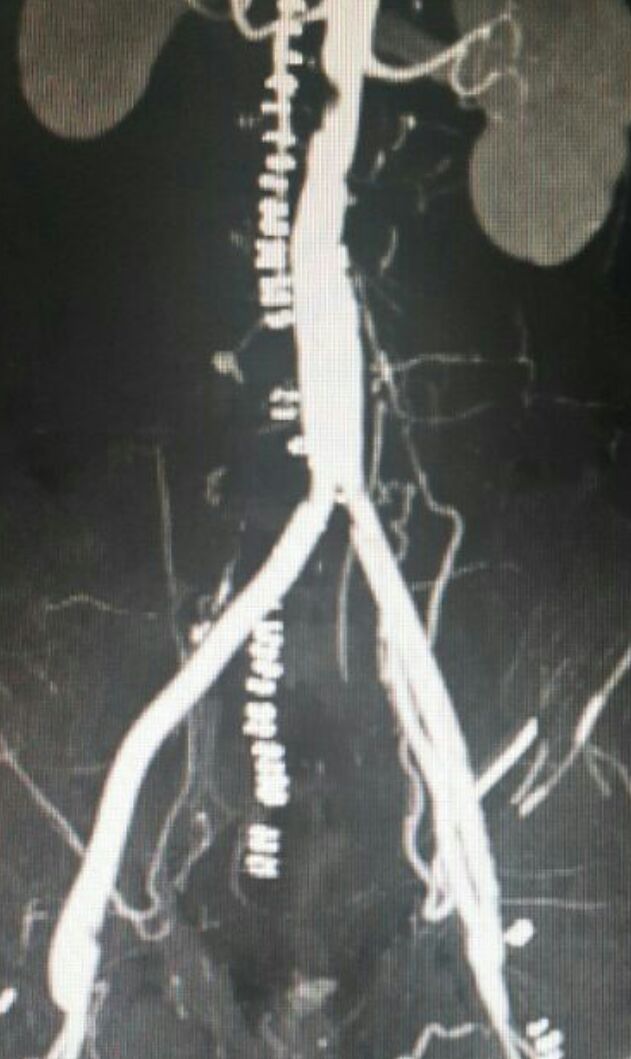

نجح فريقٌ طبي في إجراء أول عملية من نوعها في مستشفى الملك فهد، بالباحة، لاستبدال شريان الأبهر البطني بشريانٍ صناعي لمريضٍ كان يشكو من آلامٍ شديدة بالطرفين السفليّين، مع برودةٍ بالقدم، وعدم القدرة على السير.

وقال الناطق الإعلامي لصحة الباحة، ماجد الشطّي، إنه، بعد فحص المريض وعمل التصوير الطبقي للشرايين، تبيَّن وجود انسداد في الشريان الأبهر البطني، وكذلك الشرايين الحرقفية -الأيمن والأيسر- حتى الشرايين الفخذية، والمريض كان قاب قوسين من بتر الطرفين السفليّين.

كما أضاف أن العملية تمّت بوصل شريان صناعي مع الشريان الأبهر البطني، ووصله بالشريان الفخذي الأيمن والأيسر، وبهذه العملية تم إيصال الدم الشرياني إلى الطرفين السفليّين، وتجاوز منطقة الانسداد بالأبهر البطني والشريانين الحرقفيين، وبفضل الله تعالى، تم إخراج المريض من المستشفى بعد أسبوعٍ من العمل الجراحي، وهو بحالةٍ صحيةٍ جيدة، وتم إنقاذ الطرفين السفليّين من البتر المحتّم.